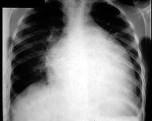

男,24岁,反复胸闷气短4年,近1周加重,端坐时即感胸闷,伴咳嗽、下肢水肿,肝脏肿大。超声心动图示心脏扩大,室壁变薄,EF值20%,二尖瓣、三尖瓣中度反流...

问题 男,24岁,反复胸闷气短4年,近1周加重,端坐时即感胸闷,伴咳嗽、下肢水肿,肝脏肿大。超声心动图示心脏扩大,室壁变薄,EF值20%,二尖瓣、三尖瓣中度反流。胸片如图所示。 若经治疗,患者病情未能好转,除下列哪项外,需要进行 ( )

选项 A、血常规查是否贫血 B、查看所用药物剂量剂型是否合适 C、加用速尿大量利尿 D、短期联合应用多巴胺与硝普钠 E、查电解质,纠正电解质紊乱

答案 D